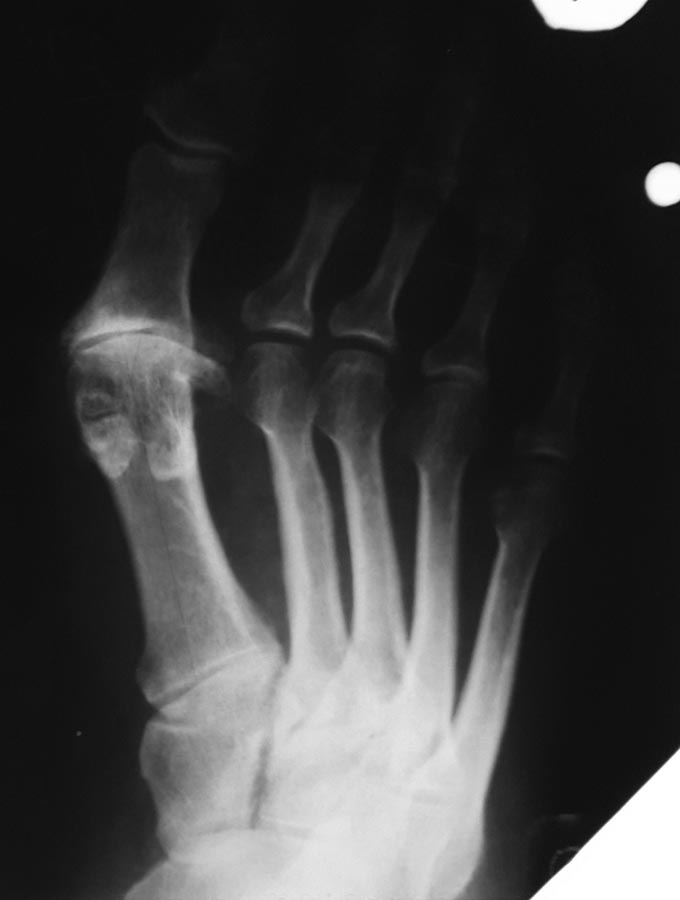

А насчет дизайна исследования (это уже Максиму). Речь в работе идет об оперированных 15 лет и больше назад пациентах. А не об оперированных в течение 15 лет. Средний срок наблюдения 14 лет. И задача исследования как раз состояла в том, чтобы сравнить эффективность двух видов остеотомий у одинаковых групп пациентов. А не подтвердить мнение "всех корифеев" о большем корригирующем потенциале scarf. Насчет рекомендаций корифеев тоже спорный вопрос. К примеру, в 2011 г. на III Международном конгрессе по малоинвазивной хирургии стопы в Брюгге целый симпозиум в рамках конгресса назывался "Шевронная остеотомия при XXXL деформациях". И еще, что за такой ориентир 20 гр.? Вполне средний угол. Особенно если речь идет о короткой и толстой М1. Я уже давно не делаю ни шевронные остеотомии, ни scarf. Но в качестве примера возможностей шевронной остеотомии во вложении - собственное наблюдение 7-летней давности. М1М2 25 гр. Пациентке 73 г. Послеоперационная рентгенограмма сделана через 2.5 мес., когда срослись остеотомии. А снимок стопы через 9 мес. А второй случай - пример относительности значения первого межплюсневого угла. Пациентка 67 лет. Гнойная рана на фоне рецидива деформации. Были выполнены хирургическая обработка раны с ушиванием наглухо и чрескожный артродез первого плюснеклиновидного сустава. М1М2 уменьшился с 31 до 19 гр. Этого оказалось достаточно для получения отличного косметического результата. И функционального. Фото стопы сделано через 18 мес. после операции. Выходит, что даже при М1М2 19 гр. стопа может выглядеть вполне симпатичной.

Сергей, по Вашей ссылке в случае Шеврона оказалась прилично укорочена М1.. PASA на вскидку около 40.. может для пожилого человека с нарушенной трофикой это и выход...

Шеврон получился отлично. А вот интересно какова причина центральной метатарзалгии при отсутствии hallux valgus? У пациентки первая плюсневая кость длиннее остальных (один из самых частых предрасполагающих к развитию артроза факторов), признаки артроза первого плюснефалангового сустава 2-3 степени. Наверняка имелась выраженная тугоподвижность ПФС1. Может с этим была связана метатарзалгия? С переносом нагрузки на наружный край стопы из-за ограничения подвижности и болезненности сустава большого пальца? В этом случае вполне можно было ограничиться укорачивающей остеотомией М1 или каким либо вмешательством на ПФС1.

И чтобы закончить тему scarf "по любому случаю" - рентгенограмма с вчерашней консультации.

Пациентка оперирована 5 лет назад известным хирургом. Scarf при маленьком М1М2 (при отсутствии первичных снимков это легко представить по ориентации основания М1 и углу наклона суставных поверхностей первого плюснеклиновидного сустава). Одно из последствий операции - неоартроз между головками М1 и М2. Я такое впервые увидел.